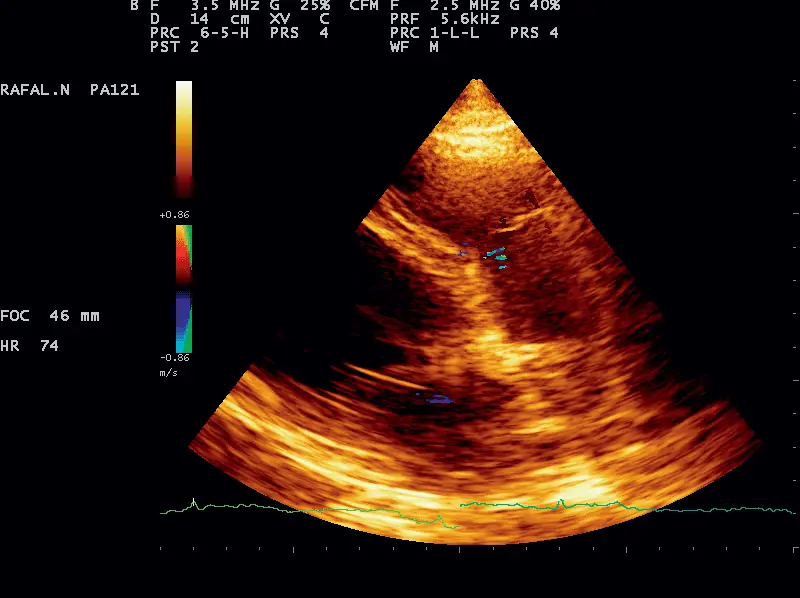

W marcu 2019 r. do przychodni trafił 11-letni owczarek środkowoazjatycki na konsultację kardiologiczną z powodu kaszlu z krwią. Pies w styczniu przeszedł operację skrętu żołądka, w czasie której usunięto śledzionę z dwoma guzkami (z dostarczonego opisu wynikało, że były to zmiany rozrostowe na śledzionie do różnicowania z nowotworem z komórek plazmatycznych). Wykonano badanie kliniczne, które jedynie w osłuchiwaniu wykazało ogniskowo w środkowo-tylnym polu płucnym po lewej stronie zaostrzony szmer oskrzelowy. Badanie kardiologiczne wykluczyło problem odsercowy. Wielkość lewej i prawej komory były prawidłowe, grubości ściany wolnej lewej komory oraz przegrody międzykomorowej były bez zmian, stosownie do masy ciała, wielkość lewego przedsionka była prawidłowa, a funkcja skurczowa lewej komory zachowana. Zastawka mitralna była bez zmian i bez niedomykalności, widoczna była jedynie śladowa niedomykalność zastawki trójdzielnej – do monitorowania raz w roku. Przepływy przez aortę i tętnicę płucną były prawidłowe, a odległość płatka zastawki mitralnej od przegrody w normie. W badaniu elektrokardiograficznym (EKG), towarzyszącym badaniu echo, nie stwierdzono nieprawidłowego rytmu serca oraz obecności dodatkowych pobudzeń (zdj. 1).